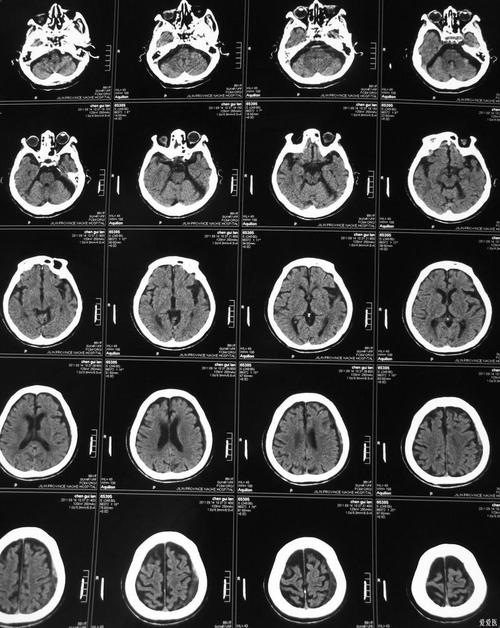

(图片来源网络,侵删)

第一步:做急诊平扫CT

- 目的:快速排除脑出血(脑出血和脑梗的治疗方案完全相反)。

- 结果:

- 如果CT显示脑出血,则绝对不能使用溶栓或取栓等治疗缺血性脑梗的方法。

- 如果CT未见出血,且高度怀疑是缺血性脑梗,那么下一步就需要寻找病因。

| 平扫CT | 看脑组织 | 可以(发病6小时后) | 初步筛查:快速排除脑出血,对早期梗塞不敏感。 |